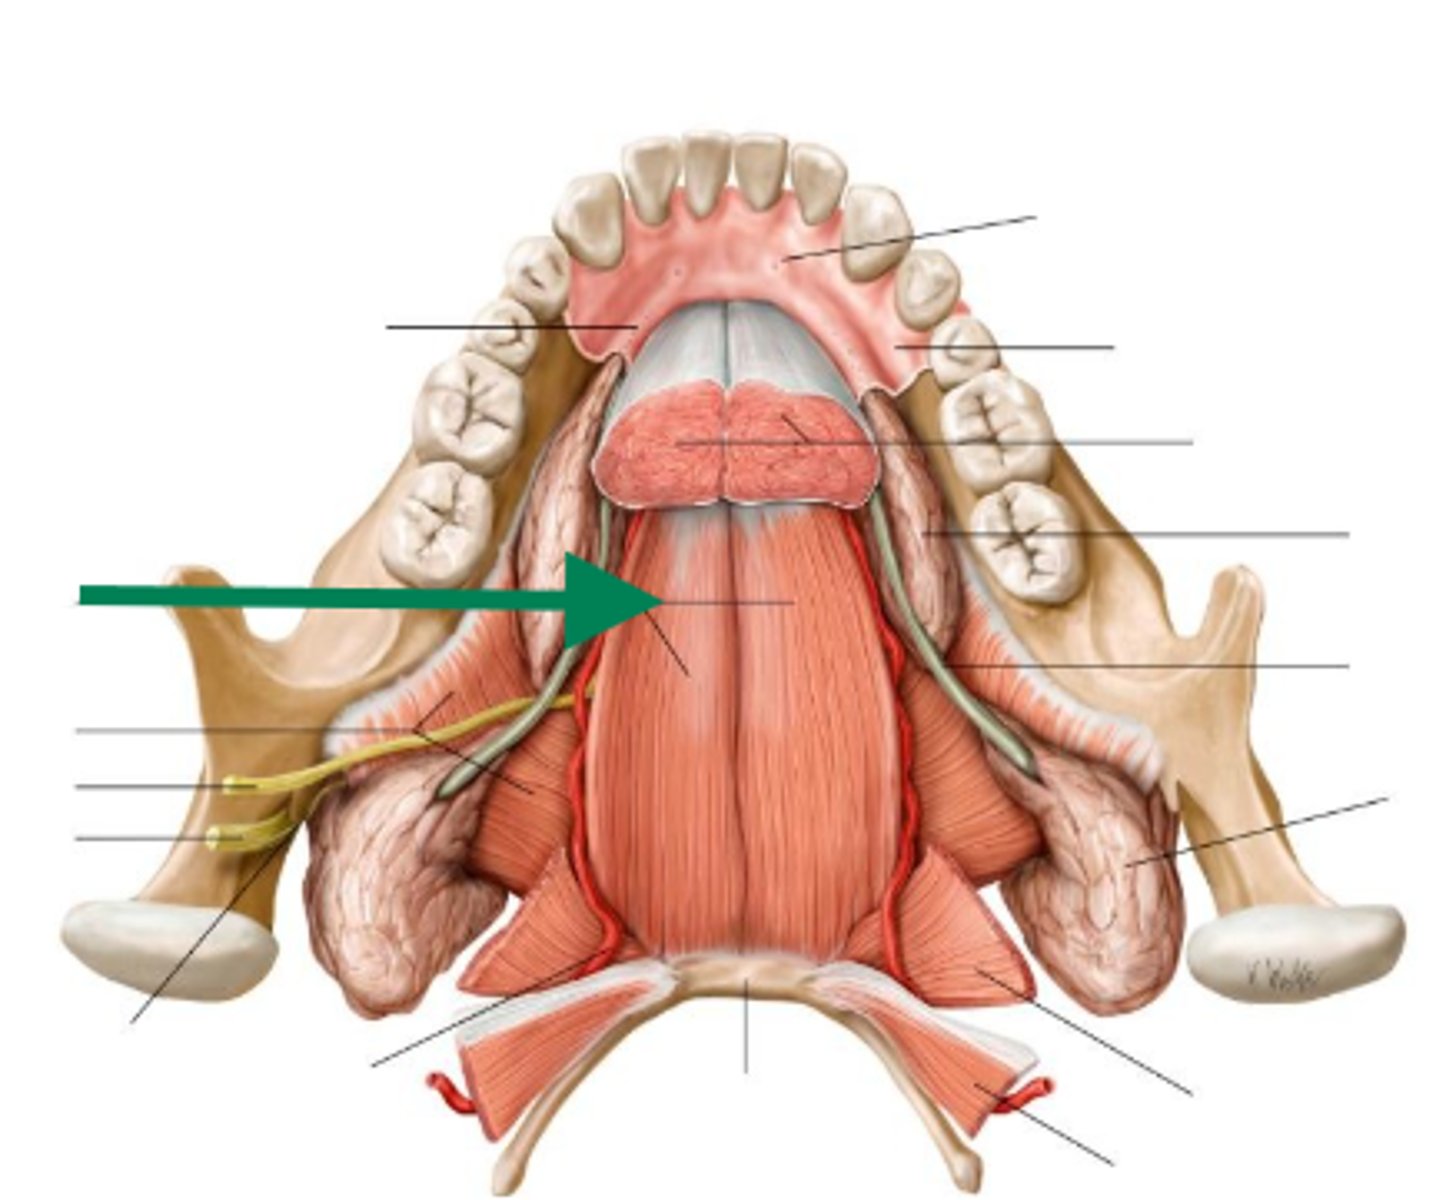

lingual nerve

lingual nerve

lingual nerve

inferior alveolar nerve

inferior alveolar artery

medial pterygoid

mental nerve

lingual nerve

buccal artery

buccal nerve

mandibular foramen

buccinator